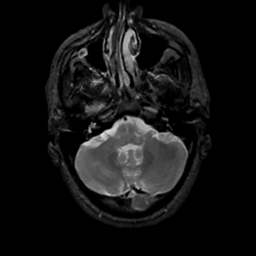

MR Study #7, March 24, 1991 -- Slice #10